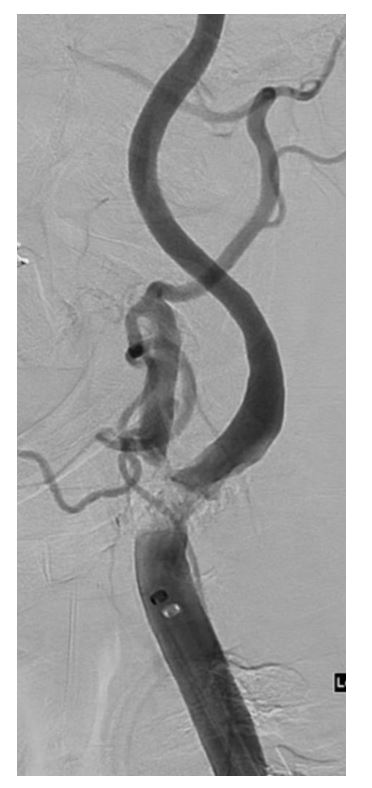

Figure 3: Digital Subtraction Angiography of Left ICA pre-stenting demonstrating heavily calcific, high grade stenosis.